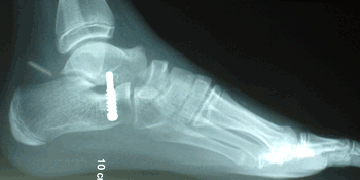

Caso 1: Pie plano esencial laxo

Haga click para agrandar las imágenes